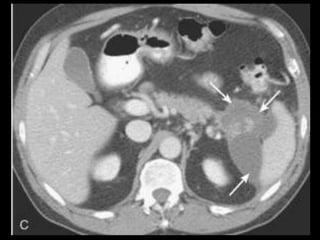

Pseudocistos-TC

Coleção líquida redonda ou oval, com uma parede

fina ou espessa, que apresenta intensificação pelo

contraste;

RM: lesão uniloculada bem definida, hipointensa

em T1 e hiperintensa em T2;

Bolhas de gás: infecção, fístula ou à cistostomia

interna;

Hemorragia aguda dentro do cisto: hiperdensa

Estenose ou oclusão venosa, com formação de

varizes ou pseudoaneurismas.